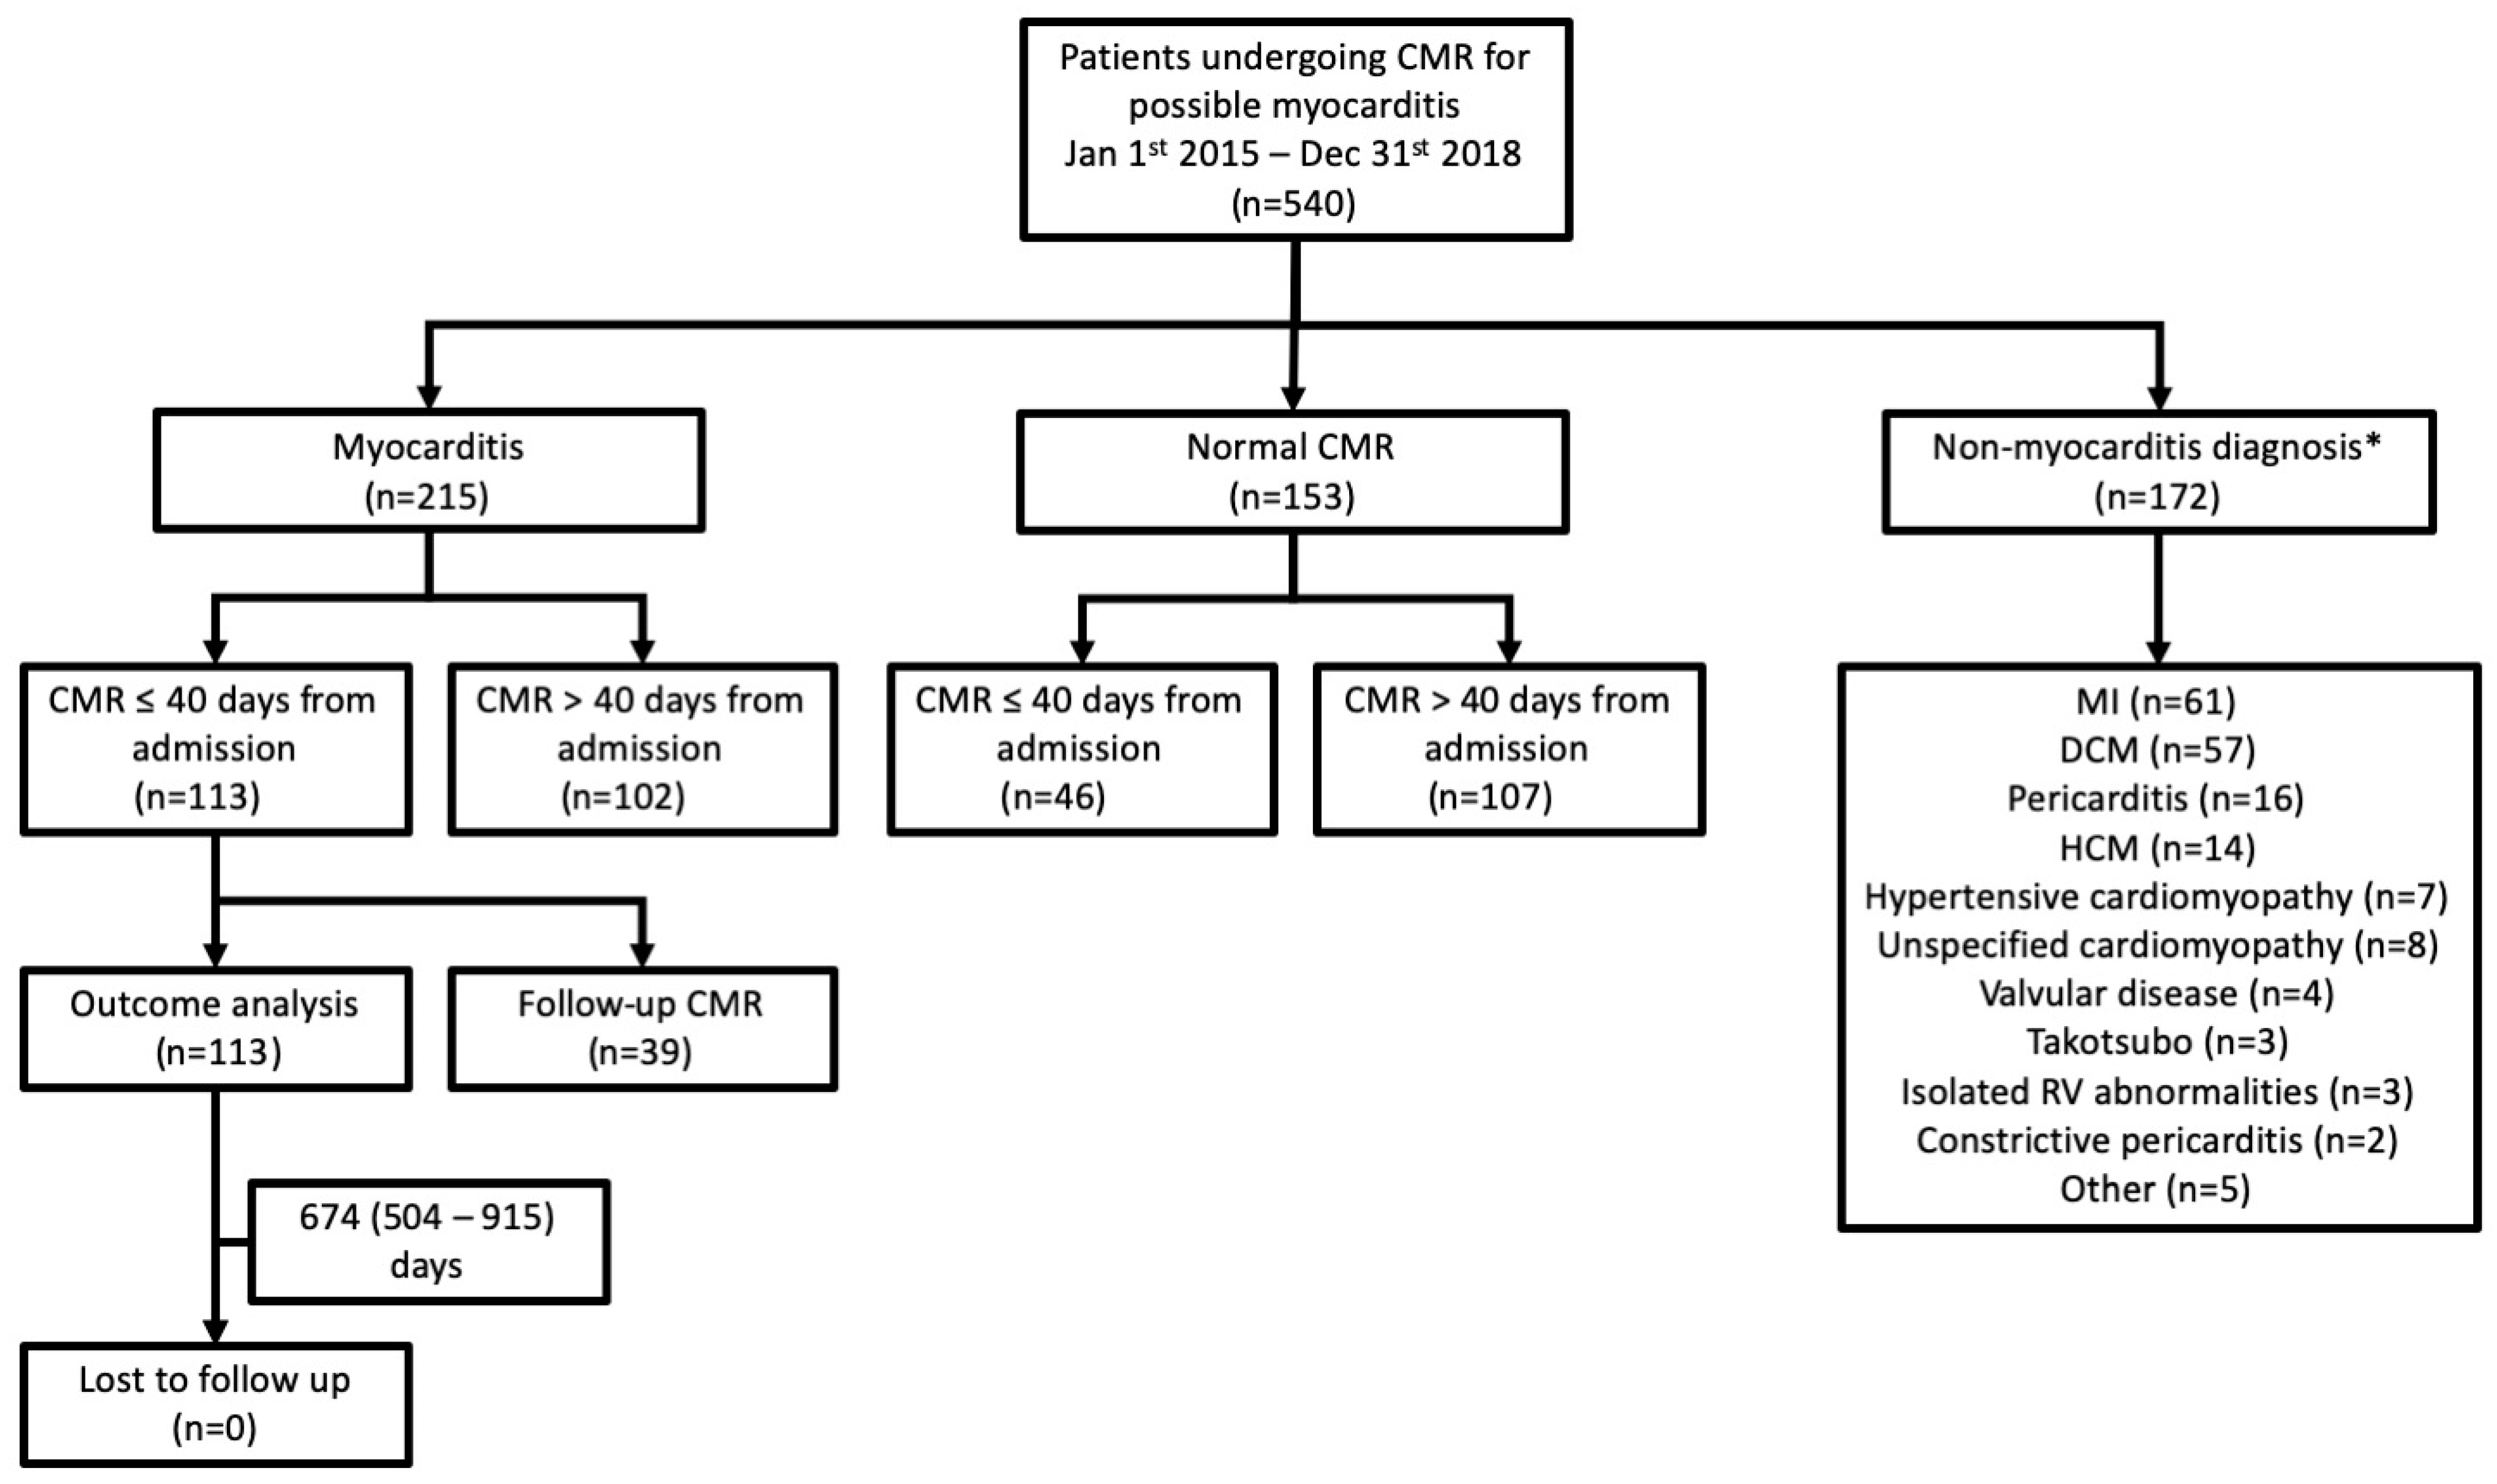

2.1. Study Design and Participants

3.1. Diagnostic Yield of CMR